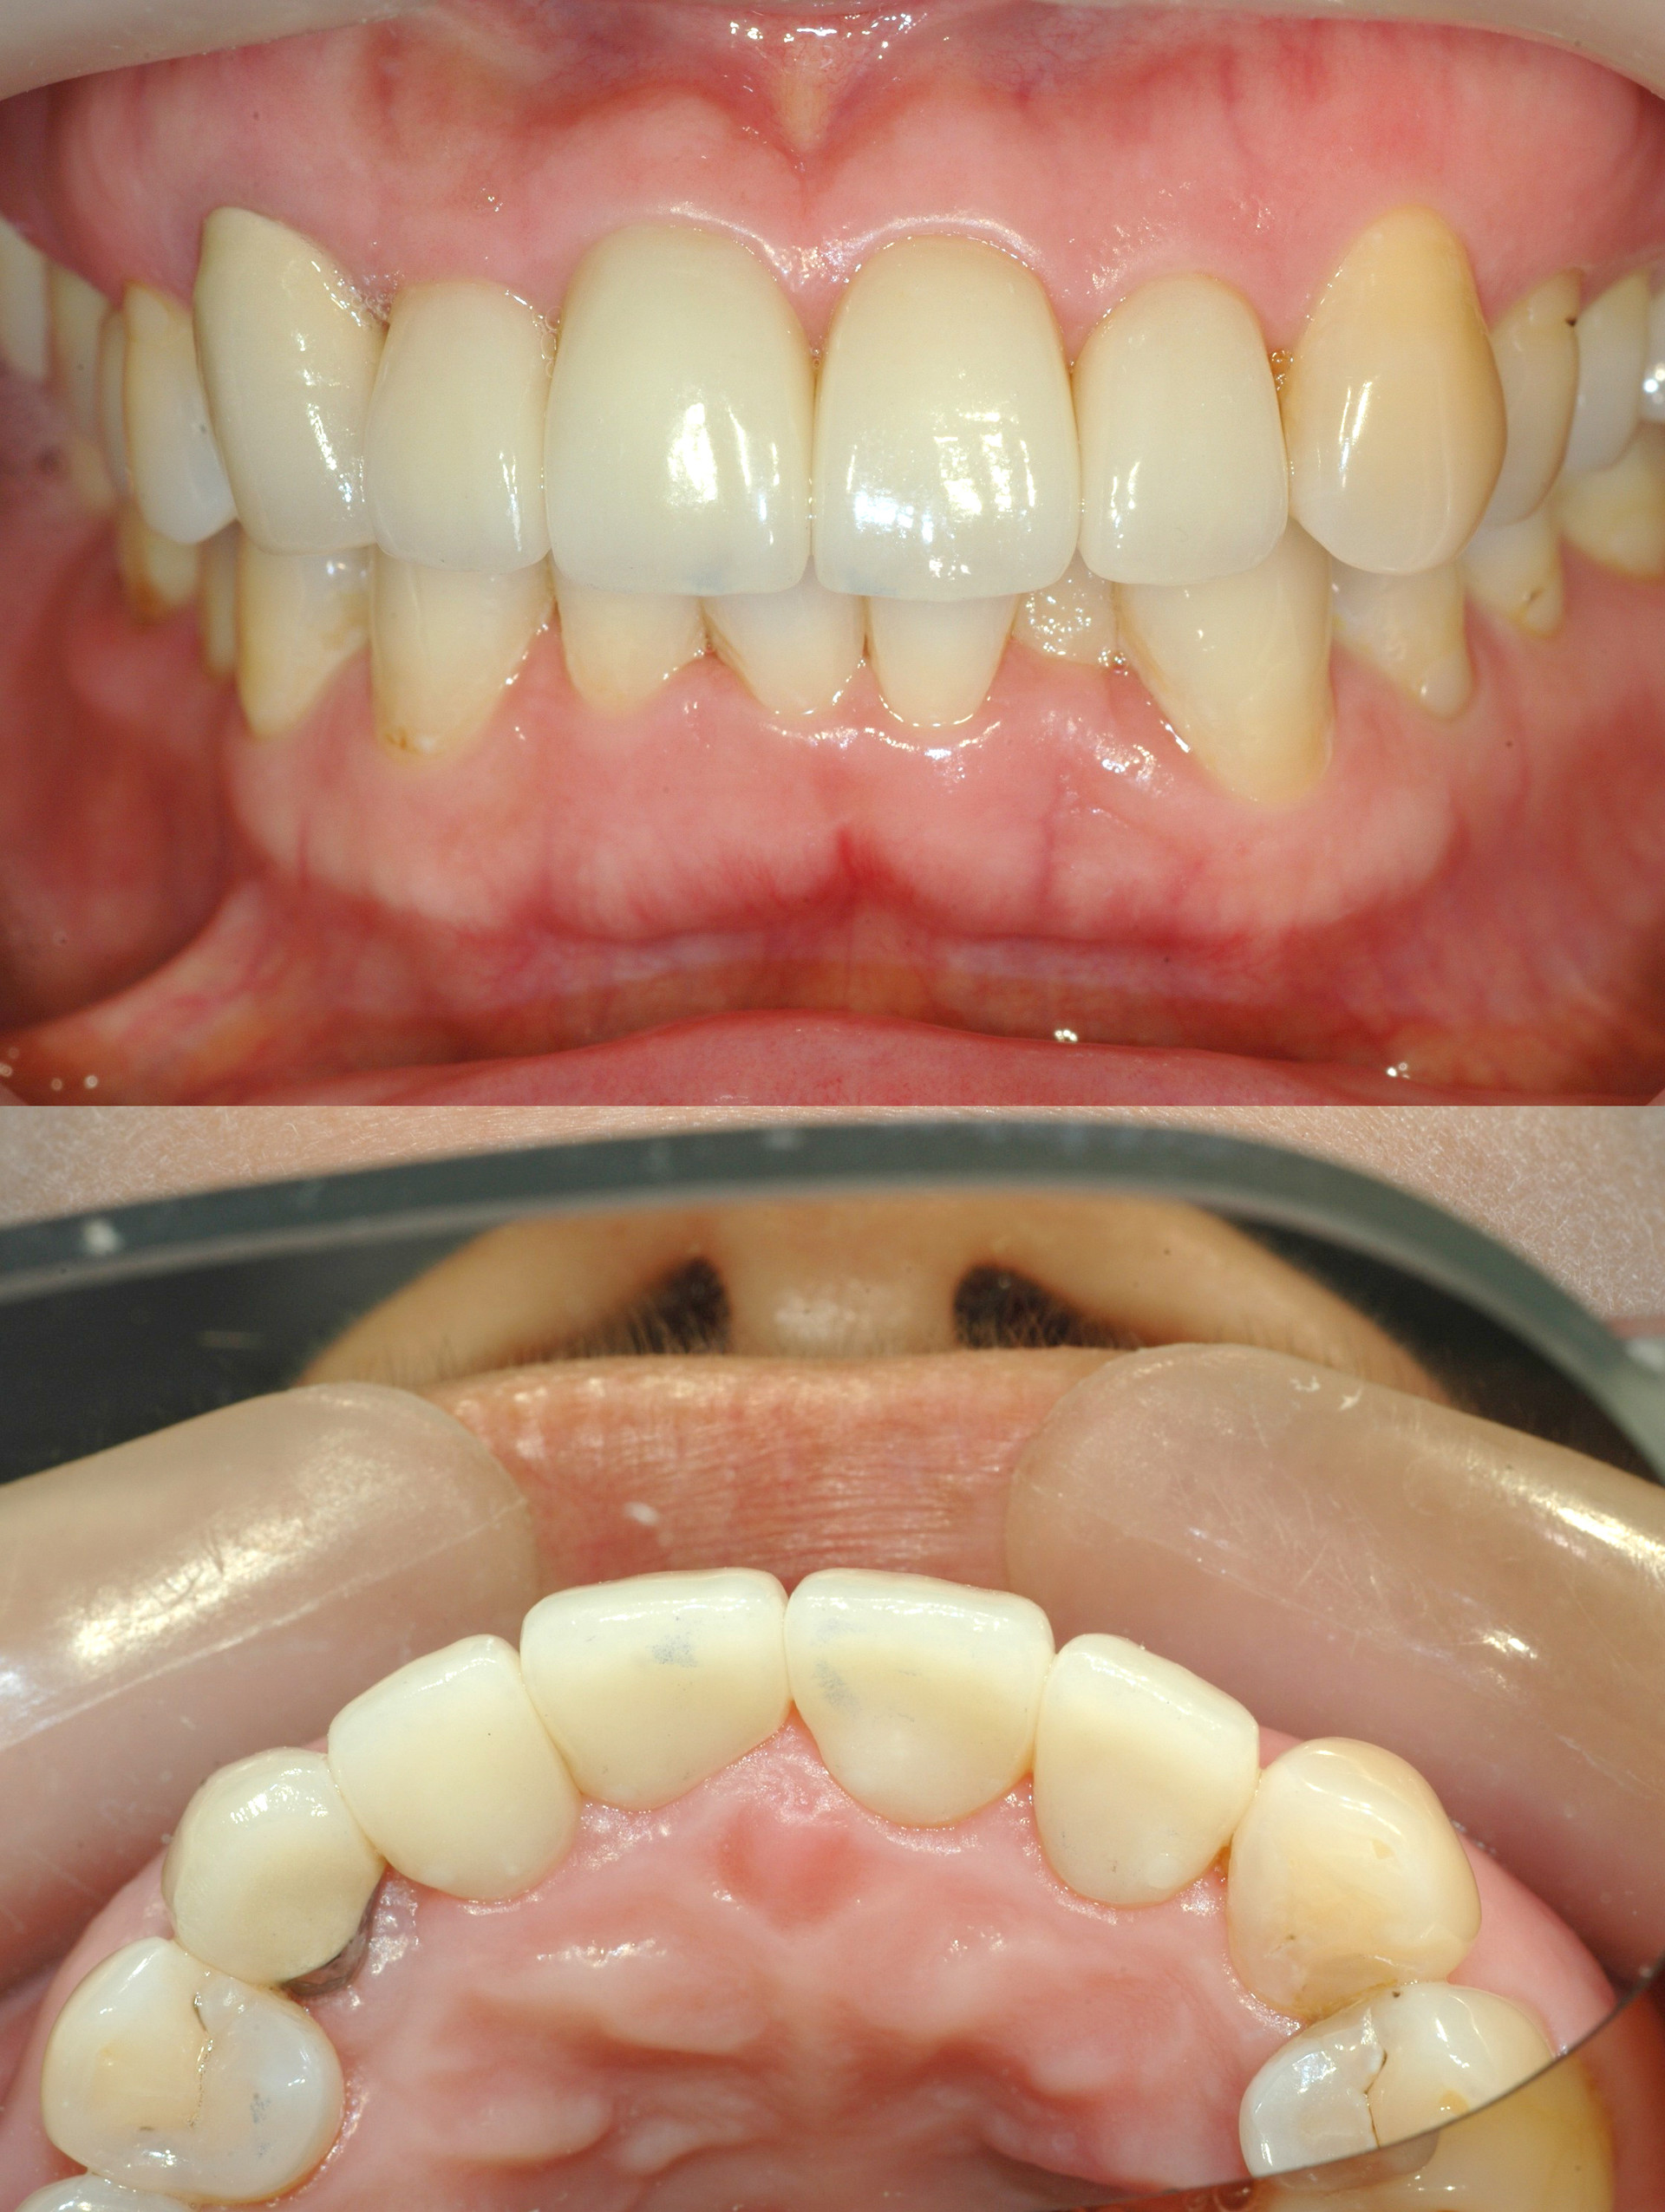

Before & After

> 토브 일반진료 사례

case 01

레진 치료

case 02

인레이 치료

case 03

전악보철

> 토브 협진치료 사례

교정+보철+치은이식

교정+임플란트

Before

라미네이트 시술 전

After

라미네이트 시술 후